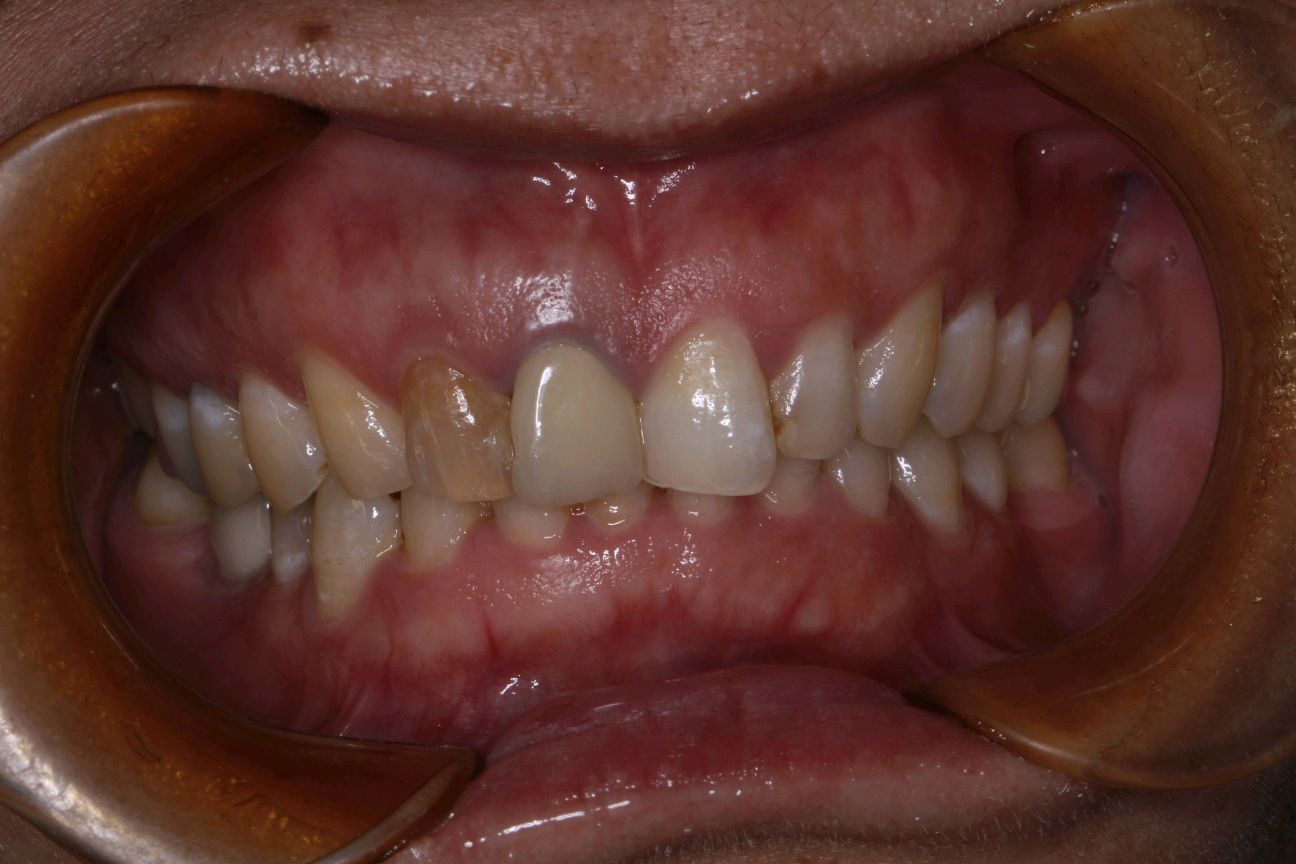

术后